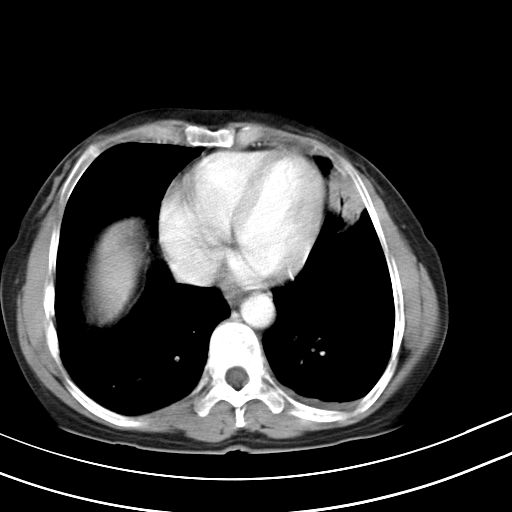

右肺上叶尖后段班片影不能出外肺结核。左肺舌叶三角形实变影,增强明显。考虑炎性病变

考虑两肺炎症,左胸腔积液,建议治疗后复查!

考虑炎性病变,左肺舌叶病灶需要与早期肺脓肿鉴别(结合实验室),左侧少量胸腔积液。

考虑两肺炎症,建议治疗后复查,左侧少量胸腔积液

1)右肺上叶前段及左肺上叶舌段感染性病变;建议抗炎治疗后复查。2)左侧少量胸腔积液。